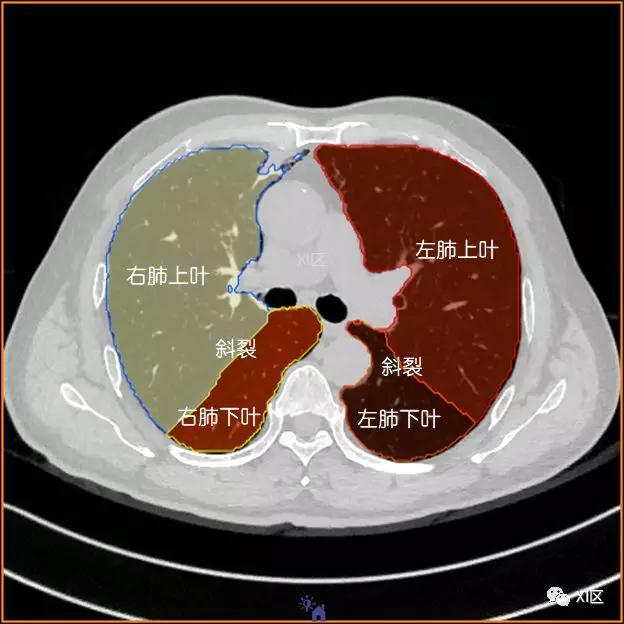

肺的分叶

左肺借斜裂成上、下两叶;右肺借斜裂和水平裂成上、中和下叶三叶。

横断位

肺的断层分段示意图

在进行肺的分段时,可以上下观察浏览,沿着相应气管的走形可以更容易准确地进行分段。